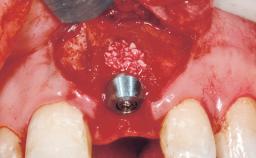

Immediate Flapless Placement of an Implant in a Maxillary Left Central Incisor Site

A 42-year-old female patient was referred to our clinic at the School of Dentistry of the University of São Paulo in November 2004, presenting a deficient restoration in the upper left central incisor. The clinical examination revealed no gingival retraction or any signs of gingival inflammation and, therefore, previous periodontal treatment was not considered. The patient presented a high lip line at full smile and a thin tissue biotype. This combination characterized a high-risk situation from an anatomic point of view, which required careful preoperative planning and cautious surgical execution.

Placement Protocol Immediate implant placement

Socket Integrity Sufficient, with intact bone walls

Bone Volume Sufficient, with intact walls

Loading Protocol Immediate